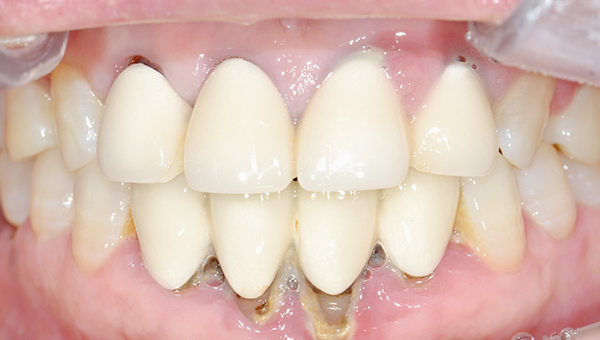

강*란 임플란트 시술 사례

전체 임플란트

2025.02.07

치료 전

2025.08.19

치료 후